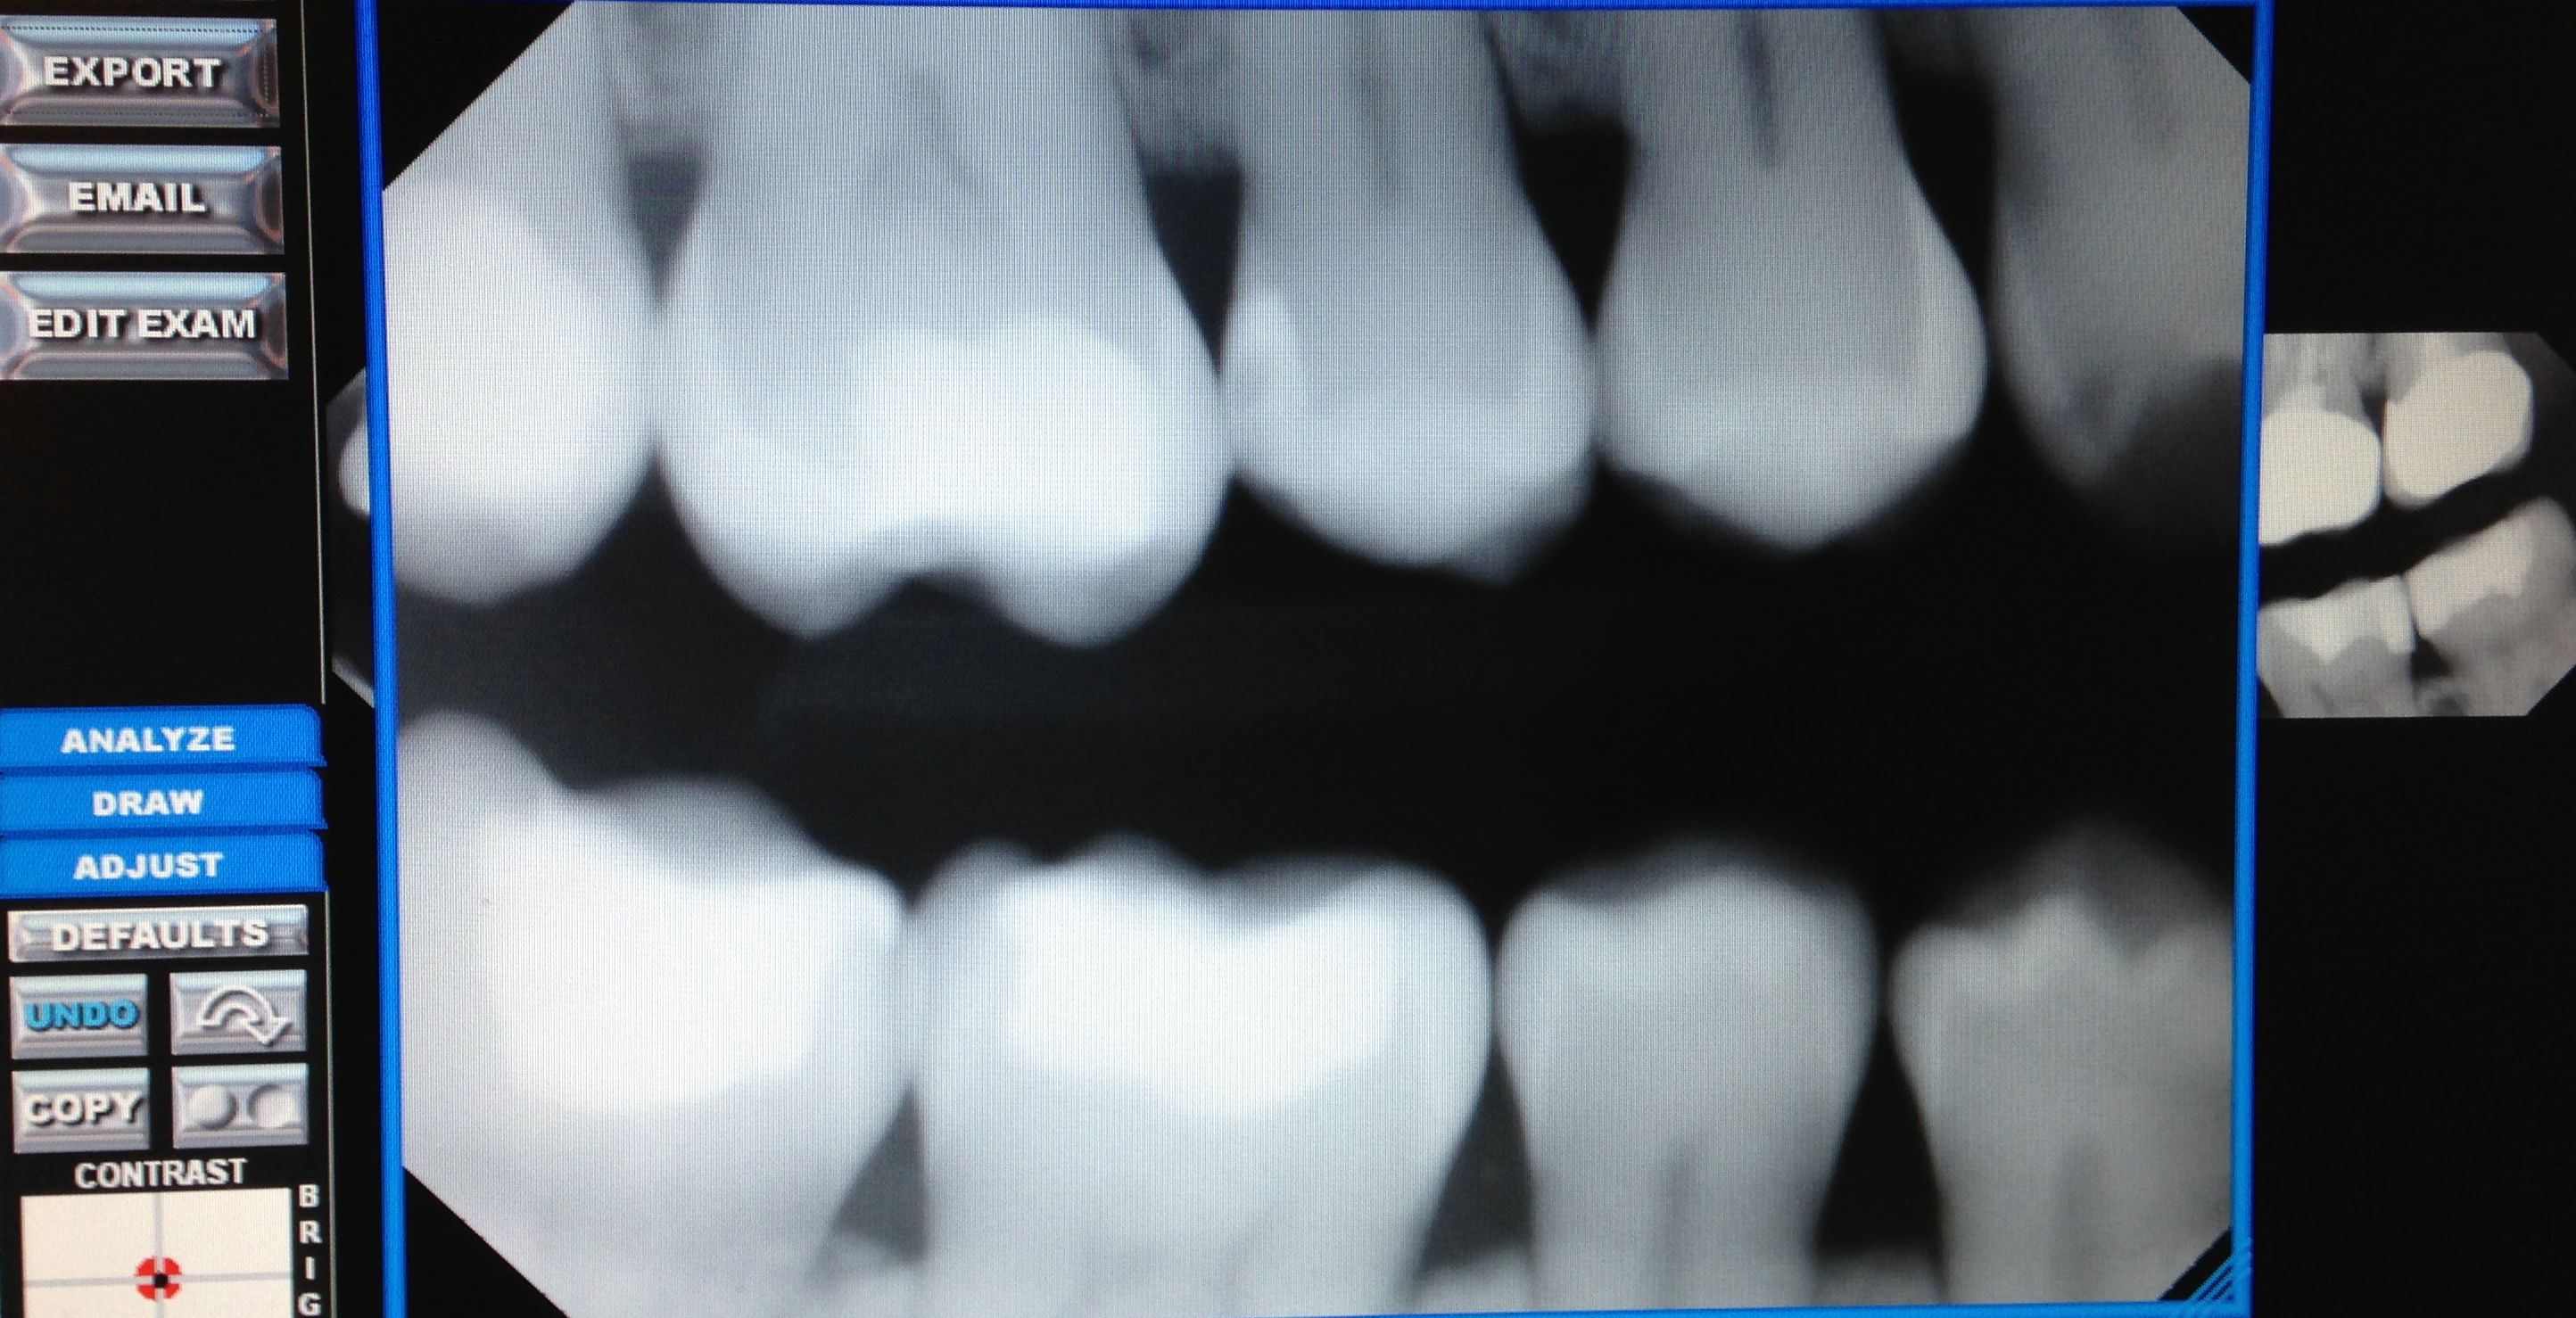

Dear E., I know that you know that I have been bad about flossing. (After all, you did find a hunk of meat jammed between my molars.) And, I’m sorry I gagged as you raced to take my x-rays; I lifted up my legs and tried to breathe through my nose, but I just wanted to get that pinching piece of plastic out of my jaw. Even more, I’m sorry you had to use the sonic water shooter on my teeth because I have been enjoying too much espresso this busy semester. Thank you for taking care of my teeth. I wish you had bubblegum flavor fluoride.